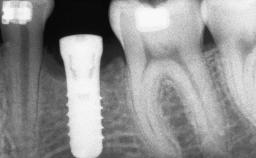

A 46-year-old woman was referred for treatment whose main complaints were mobility of her fixed partial dentures (right maxilla and left mandible) and periodontal bleeding during function. She also reported having taken systemic antibiotics to treat recurrent swelling in the area of the upper left molars. The patient had not seen a dentist for at least 2 years. She did not smoke and had no history of major systemic disease other than two minor orthopedic procedures some years back. The first-visit examination revealed poor plaque control, tooth mobility, periodontal disease, and a residual dentition widely associated with deep periodontal pockets.

Bone Augmentation Horizontal|Staged|Vertical

Augmentation Materials Autogenous chips|Autogenous block(s)|Xenogenous

Bone Volume Deficient vertically or deficient vertically AND horizontally